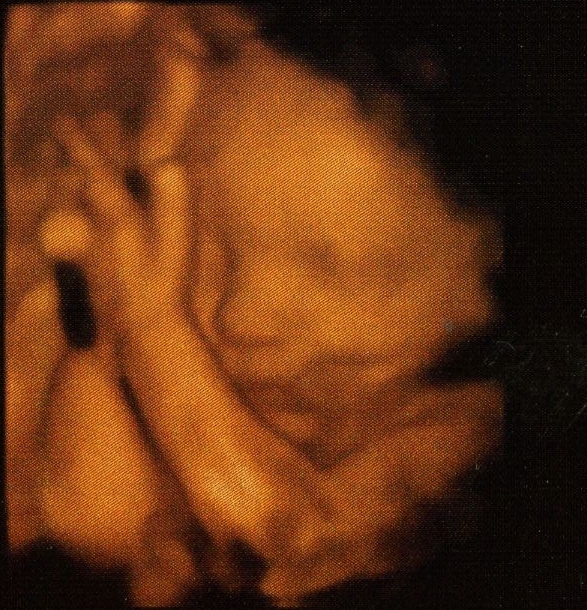

Según comentan en la clínica parece que ya hace Air guitar.

Por lo pronto parece futbolista, por las patadas que da, o sí, podría ser Air guitar, pero.

Dando saltos a lo Eddie van halen.